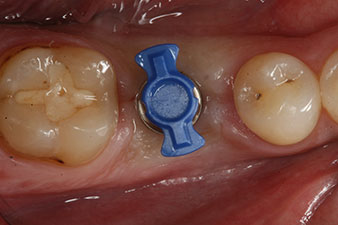

Fig. 4: SmartPeg measuring posts screwed on to measure the implant stability quotients with the integrated W&H Osstell ISQ module.

The torque used for the machine-driven placement was 43 Ncm. In addition, after screwing a measuring post (SmartPeg) specially matched to the implant, the ISQ value was measured with the probe of the W&H Osstell ISQ module.

This module is an optional extra for the W&H Implantmed and is docked to the implantology motor (see Fig. 11). The dimensionless ISQ value immediately after insertion was 64 orovestibular and 68 mesiodistal (maximum value = 100).